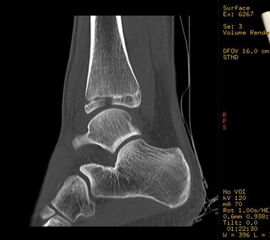

Computertomografie

Die Computertomografie liefert die höchste Auflösung für knöcherne Verletzungen und die Untersuchung dauert nur wenige Sekunden. Nachteilig ist die hohe Strahlenbelastung, die bei einem Vielfachen von konventionellen Röntgenbildern liegt. Bei komplexen Gelenksfrakturen hat die Computertomografie aber auch beim Kind ihre Berechtigung und erleichtert die Planung der Rekonstruktion.

Der teilweise komplexe Frakturverlauf bei Übergangsfrakturen lässt sich im CT zuverlässig darstellen 10. Der erfahrene Untersucher kann bereits mit Röntgenaufnahmen des Sprunggelenks in zwei Ebenen in Verbindung mit zwei 45° Schrägaufnahmen sehr umfassende Aussagen zum Frakturverlauf treffen (v. Laer 2013), die Präzision und Aussagekraft der Computertomografie ist aber zweifelsohne überlegen und wird von den meisten Behandlern bevorzugt 11, auch wenn sich zu diesem Thema in der Literatur eine teilweise sehr emotional geführte Diskussion findet. Einigkeit hinsichtlich der Indikation für ein Schnittbildverfahren besteht bei Triplane-Frakturen, wenn Zweifel darüber bestehen, inwieweit die metaphysäre Fraktur den tragenden Gelenkanteil tangiert 12.

Dislozierte Frakturen (Frakturspalt > 2 mm) werden grundsätzlich operativ behandelt. Die Reposition kann arthroskopisch unterstützt erfolgen. Die Schraubenosteosynthese erfolgt entsprechend dem Frakturverlauf. Bei Twoplain Frakturen ist meist eine epiphysäre Schraube ausreichend die von lateral kommend das Fragment nach medial-proximal fixiert. Der Schraubenverlauf ist üblicherweise von lateral ventral nach proximal dorsal medial (Abb. 24). Nach Reposition darf in der seitlichen Aufnahme des Sprunggelenks, als auch in der 45° Außenrotationsaufnahme keine Stufe in Höhe der Wachstumsfuge erkennbar sein. Eine sichtbare Stufe ist Indikator für eine unzureichende Reposition.

Bei Triplane-Frakturen fasst die metaphysäre Schraube das metaphysäre Fragment einschließlich eines hinteren Volkmann Dreiecks, die epiphysäre Schraube fasst das epiphysäre Fragment. Da der Fugenschluss noch nicht abgeschlossen ist, sollten die Schrauben die Wachstumsfuge nicht kreuzen, obwohl eine Wachstumsstörung unwahrscheinlich ist (v. Laer 2013).